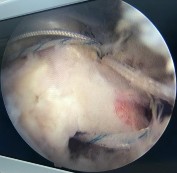

Hình phụ lục 2B:Hình ảnh rách rất rộng gân trên gai, dưới gai, khoảng gian chóp xoay; hình ảnh khâu khép rìa gân rách.

(Nguồn: BN nghiên cứu)

Hình phụ lục 2C: Hình ảnh xác định vị trí đặt 02 neo. (Nguồn: BN nghiên cứu)